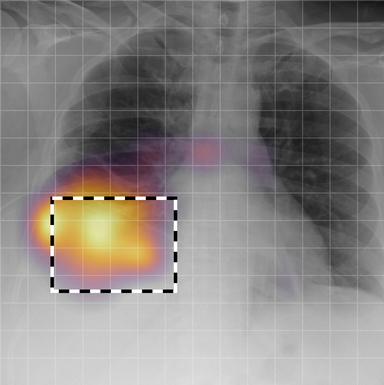

| (1) |

for , where denotes 2D sinusoidal positional encodings [12] and is its temporal counterpart, which is learnt (Fig. 2) [4]. The layer-normalised () [6] output of the final transformer encoder block is an ‘aggregated’ representation of patch-level progression information anchored on the current image. Figure 3 shows attention roll-out [1] applied to after pre-training, showing how the prior image contributes to the fused representation. Figure A.5 further highlights the robustness to variations in pose underlining that registration is not necessary for this encoder.

In Figure A.3, we show examples of self-attention rollout [1] maps for pleural effusion and consolidation, including radiologist-annotated bounding boxes surrounding the corresponding pathology in each prior and current image.

To model the attention flow through the transformer encoder block, we first average each attention weight matrix across all heads, subsequently we multiply the matrices between every two layers. For every block we add the identity matrix in order to model the residual connections. Last, we only keep the top 10 of attention weights per block to reduce noise in the final rollout map. In contrast to [21], we do not visualize the rollout map with respect to a [CLS] token. Instead, we choose a reference image patch from the center of the radiologist-annotated bounding boxes, marked with in Figure A.3.

We find that the rollout maps in Figure A.3 are in good agreement with radiologist-annotated bounding boxes, i.e., the reference patch attends to other patches within the bounding boxes in the prior and current image. In addition, we find that BioViL-T is robust to pose variations, e.g., in Figure A.3 (a) we show that despite the vertical shift between prior and current image, the reference patch attends to the correct image patches in the prior image.